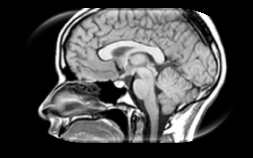

Causal machine learning (CML) has experienced increasing popularity in healthcare. Beyond the inherent capabilities of adding domain knowledge into learning systems, CML provides a complete toolset for investigating how a system would react to an intervention (e.g.\ outcome given a treatment). Quantifying effects of interventions allows actionable decisions to be made whilst maintaining robustness in the presence of confounders. Here, we explore how causal inference can be incorporated into different aspects of clinical decision support (CDS) systems by using recent advances in machine learning. Throughout this paper, we use Alzheimer's disease (AD) to create examples for illustrating how CML can be advantageous in clinical scenarios. Furthermore, we discuss important challenges present in healthcare applications such as processing high-dimensional and unstructured data, generalisation to out-of-distribution samples, and temporal relationships, that despite the great effort from the research community remain to be solved. Finally, we review lines of research within causal representation learning, causal discovery and causal reasoning which offer the potential towards addressing the aforementioned challenges.